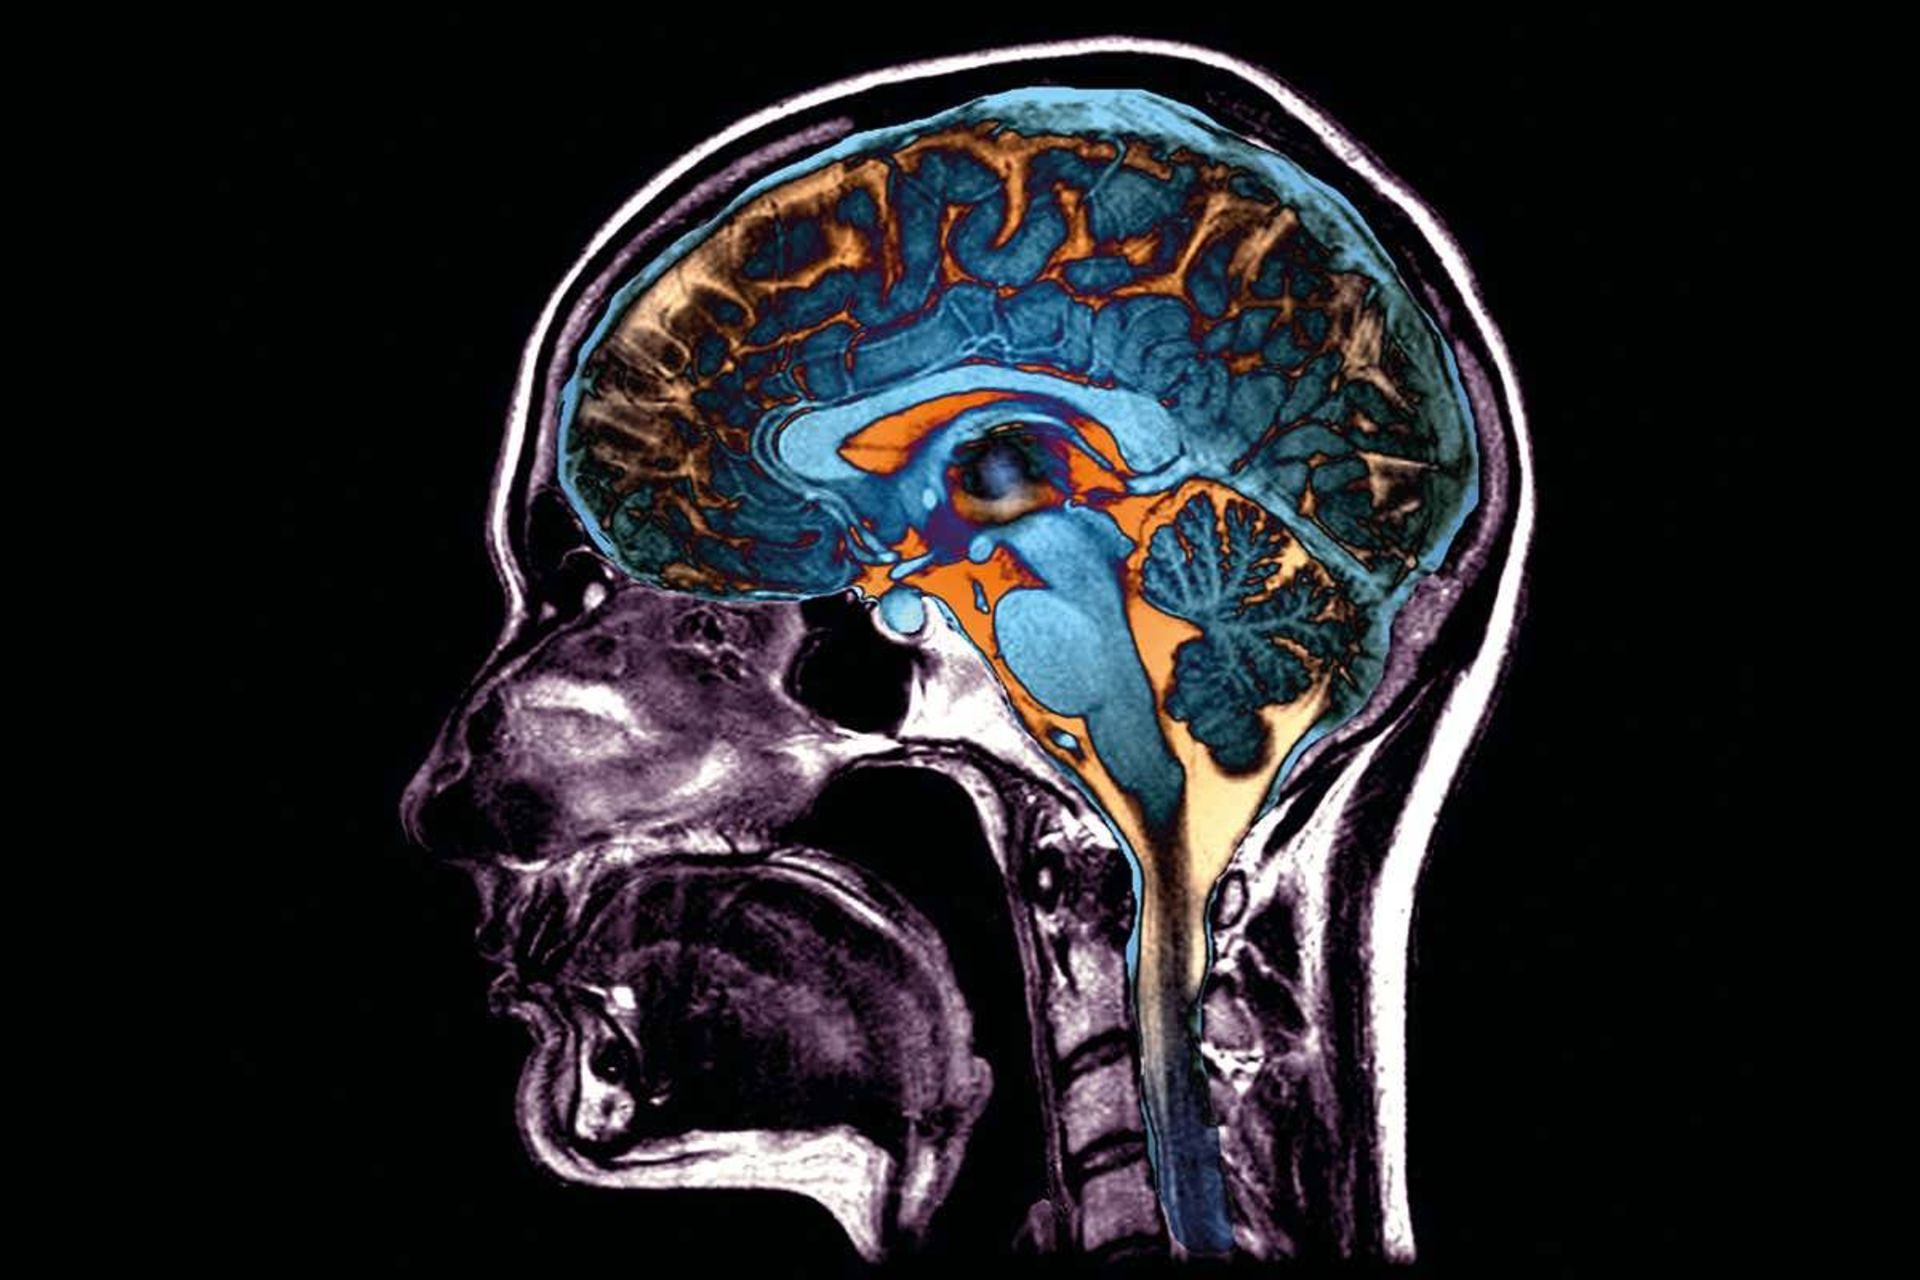

اسکن مغز بیماران کووید ۱۹

اسکن‌های مغز بیماران مبتلا به کووید ۱۹ از مطالعه‌ای که در ماه جولای منتشر شد. دانشمندان متوجه شدند برخی از بیماران دچار عوارض عصبی جدی نظیر آسیب عصبی می‌شوند